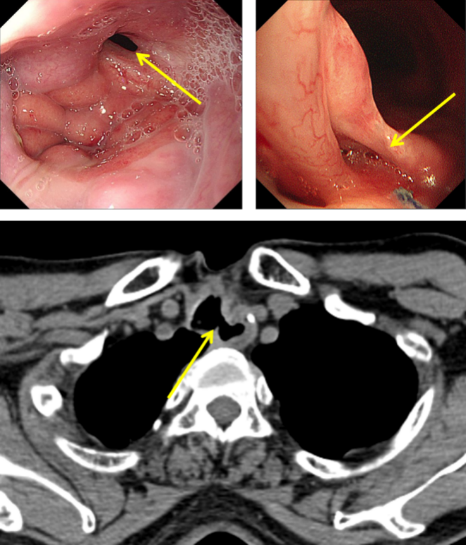

圖1:氣管食管瘺口

經(jīng)推薦,老秦慕名來到我院胸外科胡楊副主任醫(yī)師處就診。經(jīng)檢查發(fā)現(xiàn),老秦的病情與其他氣管食管瘺患者相比,更為復雜和嚴重:一是瘺口所處位置較為“刁鉆”。患者氣管食管間瘺口位于頸胸交界部位,無論是從頸部或是胸部入路均難以充分暴露瘺口;二是瘺口情況較為糟糕。該患者于外院多次行瘺口修補手術,瘺口附近勢必粘連嚴重、組織結(jié)構(gòu)難以辨認,損傷喉返神經(jīng)、頸胸部血管等重要結(jié)構(gòu)的風險高;組織血供破壞嚴重,術后缺血壞死風險高;三是患者營養(yǎng)嚴重不足。該患者由于“氣管食管瘺”已兩年未經(jīng)口進食,身體非常虛弱。

圖2:術中情況(左)喉返神經(jīng)監(jiān)測儀監(jiān)測喉返神經(jīng),(右)離斷氣管暴露食管瘺口;

(下)術后CT顯示原氣管食管間瘺口已修補。